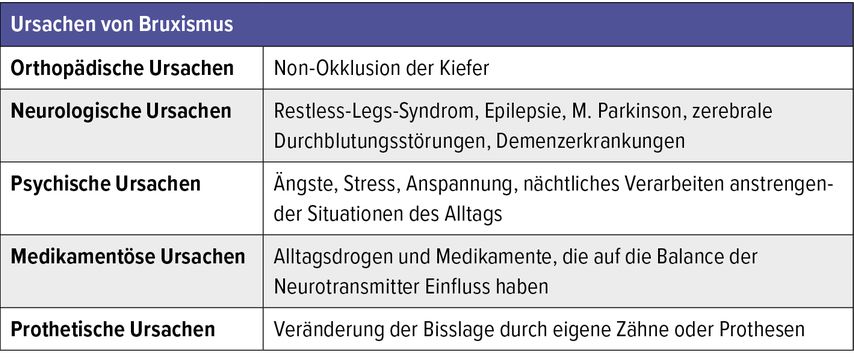

Bruxismus ist ein komplexes medizinisches Phänomen, das nicht auf eine Handvoll Ursachen reduziert werden kann (Tab.1). Seine Ursachen setzen sich aus dem individuellen Befinden, dem Lebensstil und dem Umfeld des Betroffenen zusammen. Bruxismus gilt als eines der ersten Symptome von Kiefergelenkserkrankungen.

Orthopädische Ursachen

Bei einem fehlerhaften Biss oder einer Non-Okklusion der Kiefer wird die Entstehung von Bruxismus gefördert, indem die obere und untere Zahnreihe gegeneinander reiben, weil die Zähne nicht genügend Platz haben, um sich korrekt einzufügen. Daraus resultiert ein erhöhter Muskeltonus, der an das Kiefergelenk übertragen wird und die Kaumuskulatur fehlbe- bzw. überlastet.

Neurologische Ursachen

Insbesondere für Wachbruxismus werden Zusammenhänge mit neurodegenerativen Erkrankungen beschrieben. Ursache können auch zerebrale Durchblutungsstörungen oder zerebrale Blutungen sein. Dabei scheint die gestörte Regulation der Muskelaktivität durch die Übermittlung der Signale an den Synapsen durch eine gestörte Neurotransmitteraktivität die zentrale Rolle zu spielen.2

Psychische Faktoren

Ursächlich für Bruxismus können auch zentralneurologische und psychogene Faktoren sein, wie beispielsweise starke seelische und geistige Anspannung, körperlicher und emotionaler Stress, Depressionen oder Angstzustände. Diese werden während des Schlafs, in der Zeit, in der das Bewusstsein ruht, verarbeitet. Auch Reize aus der Umwelt (z.B. anhaltender Lärm), welche die neuralen Verbindungen tagsüber in Anspannung versetzen, müssen vom Gehirn in der Nacht verarbeitet werden und können ihr Ventil über Zähneknirschen finden.

Medikamentöse Ursachen

Psychotrope Medikamente oder übermässiger Genuss von Alltagsdrogen wie Kaffee, Nikotin oder Alkohol können auf die Balance von Neurotransmittern wie Dopamin, Serotonin und Adrenalin und damit wiederum auf die Reizübertragung Auswirkungen haben.

Prothetische Ursachen

Wenn ein einheitlicher Zusammenbiss zwischen Ober- und Unterkiefer nicht möglich ist, liegt die Ursache unter Umständen im natürlichen Gebiss, z.B. bei verlagerten Weisheitszähnen, die gegen die Zahnreihe drücken und die Bisslage verändern. Bereits eine Abweichung von 0,01mm kann vom Kiefergelenk wahrgenommen werden. Daher werden auch Kronen, Brücken oder Prothesen, die nicht perfekt angepasst sind, als mögliche Ursachen von Bruxismus angesehen.